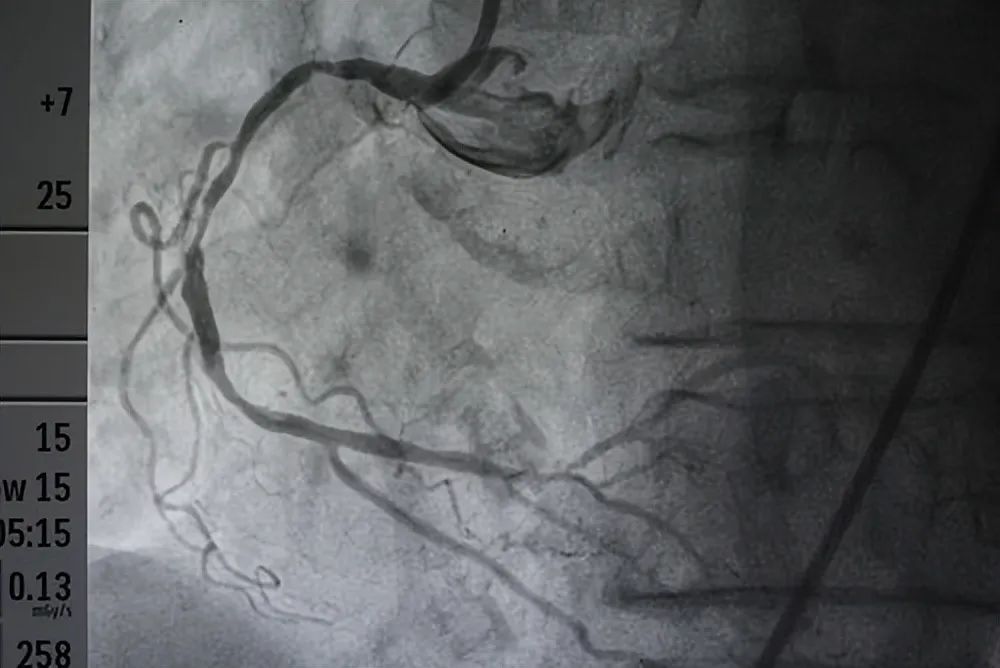

如果只能通过造影诊断冠心病,那么心血管医生谁也能当,患者到医院说难受,“医生”说:去吧,做个造影看看。首先告诉大家,造影并不是检查心脏病最准确的方法。造影只是检查冠心病目前最准确的方法。而心律失常、瓣膜病、心肌病、心衰等等心脏病即使做造影也是无法诊断的。

必要时,可以通过冠脉CTA来诊断心血管有没有狭窄,来诊断冠心病。

3、必要时再做造影

比如说急性心肌梗死,或者已经高度怀疑心绞痛要进行进一步治疗,或者新出现的完全性左束支,无法确诊的心衰,没有找到原因的心律失常等等才需要造影检查,而不是说:不舒服,就去做个造影吧。二、治疗冠心病靠什么?